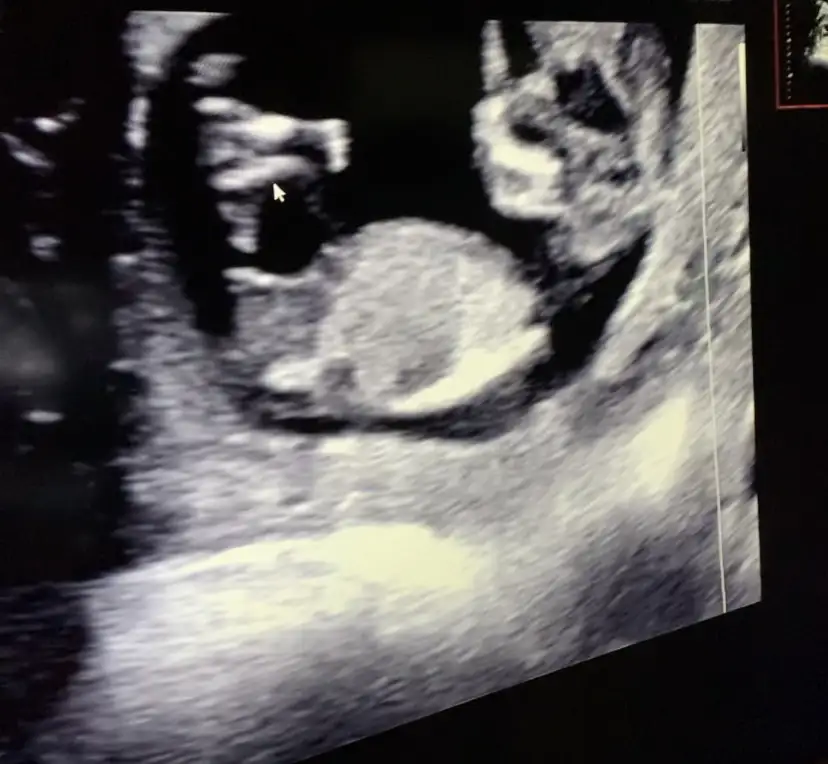

Ikra meyra canım 11+4 karından ultrason görüntümüz.Bi tahmin rica etsem

Eklentiler

• IMG_20210512_140730.webp

36,1 KB · Görüntüleme: 83

• IMG_20210512_140725.webp

36,5 KB · Görüntüleme: 95